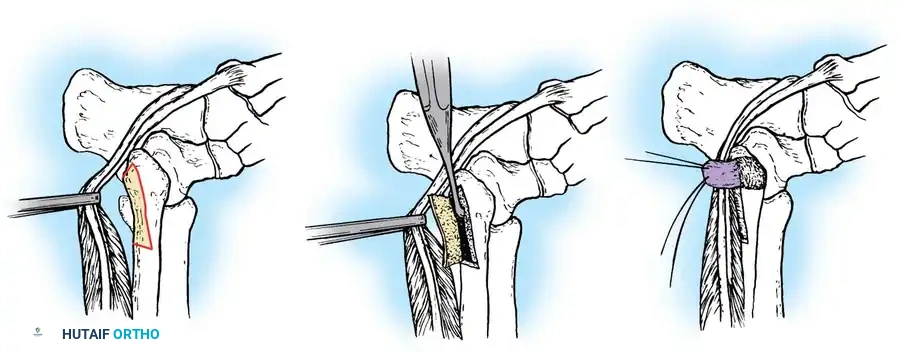

5. Tendon Repair Based on Tear Grade

For Grade I Tears (≤ 50% involvement):

If the tear involves less than 50% of the tendon's cross-sectional area, excise the smaller, degenerative section of the tendon completely. The remaining viable portion is then tubularized to restore a smooth gliding surface. This is achieved using a running 3-0 absorbable, braided suture, burying the knots to minimize friction.

For Grade II Tears (> 50% involvement):

If more than 50% of the peroneus brevis tendon is disrupted and fissured, the remaining section is generally too attenuated to be tubularized effectively. In this scenario, resect the entire diseased segment of the peroneus brevis.

Perform a side-to-side tenodesis of the proximal and distal stumps of the peroneus brevis to the intact peroneus longus tendon.

* The proximal tenodesis should be performed well above the level of the SPR, approximately 3 to 4 cm proximal to the ankle joint, generally at the musculotendinous junction of the peroneus brevis.

* Complete the repair using 2-0 nonabsorbable, braided sutures (e.g., Ethibond or FiberWire), ensuring appropriate tension is maintained to preserve eversion strength.

6. Closure

Distally, leave the tendon sheaths for both the brevis and longus open to prevent postoperative stenosis. Suture the brevis and longus tendons together distally with 2-0 nonabsorbable sutures if a tenodesis was performed.

Repair the superior peroneal retinaculum over the tendons using 2-0 absorbable sutures, ensuring the tendons do not subluxate during passive dorsiflexion and eversion. Leave the remainder of the tendon sheath open. Close the subcutaneous tissues and skin in a standard layered fashion.